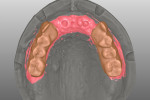

The generated standard tessellation language (STL) files were overlapped and imported into a CAD software (exocad® DentalCAD, exocad GmbH, exocad.com) coupled with a CAM milling unit (Tizian Cut eco plus; Schütz Dental Group, schuetz-dental.de) (Figure 7). Prosthesis prototypes were milled from prefabricated polymethyl methacrylate (PMMA) blocks (ZCAD™ Temp-Fix 98, Harvest Dental Products, harvestdental.com) (Figure 8).

At the next clinical visit, try-in of the PMMA prostheses was performed, followed by confirmation of esthetics and phonetics after minor modifications. The adjusted PMMA prototypes were scanned again and the CAD files were used to mill three maxillary FDPs (Figure 9) and three mandibular FDPs. Minor facial cutback was incorporated on the maxillary FDPs and the anterior mandibular FDP for porcelain veneering to enhance the esthetics. The definitive prostheses were milled (Tizian Cut eco plus) from zirconia monoblocks (Katana™ Zirconia HT, Kuraray Noritake Dental Inc, kuraraynoritake.com) and tried in (Figure 10). Feldspathic porcelain was used to veneer the facial aspect of the FDPs. Mutually protected occlusion with anterior guidance was the prescribed occlusal scheme.